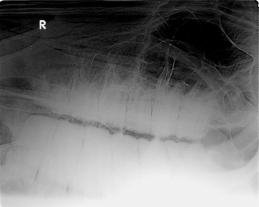

Nach der Behandlung wurden Röntgenaufnahmen von den kariösen Oberkieferbackenzähnen gemacht, um den

Wurzelbereich abzuklären. Die Kaufläche zeigte sich nach Zahnbehandlung „gleichmäßig wie beim Wildpferd“ verglich Zwick. Die hintere Hälfte des dritten sowie der vierte, bis sechste Backenzahn stehen mit den Wurzeln in der Kieferhöhle. Die ersten beiden stecken nur im Kieferknochen. Die Zähne sind unterschiedlich lang. Die ersten drei haben Milchzahnvorläufer. Der vierte ist der älteste Zahn im Gebiss, da er der erste bleibende Zahn ist. Karies ist hier als leichter Schatten am Röntgenbild noch zu erkennen. Rechtsseitig zeigt der erste Backenzahn eine kleine Abnormität: Seine Wurzel zeigt ein Ausziehung nach vorne und im Wurzelbereich eine kleine dunkle Verschattung.

Jeder einzelne Zahn und die Begrenzungen wurden begutachtet, rechts begonnen. Parodont, Zahnhalteapparat zwischen Alveole (Zahnfach) und Zahn. Die Wurzel des vierten Backenzahnes lenkt noch die Aufmerksamkeit von Dr. Zwick auf sich.